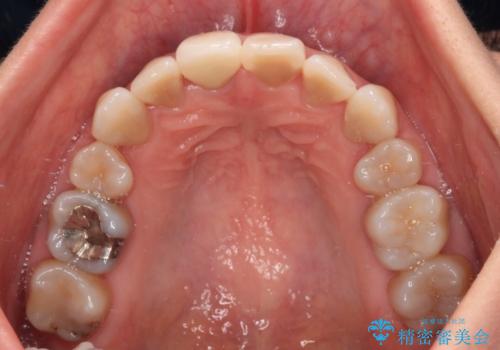

神経組織が健全な状態で残っている歯であったため、1ヶ月かからずに治療を終えることができました。